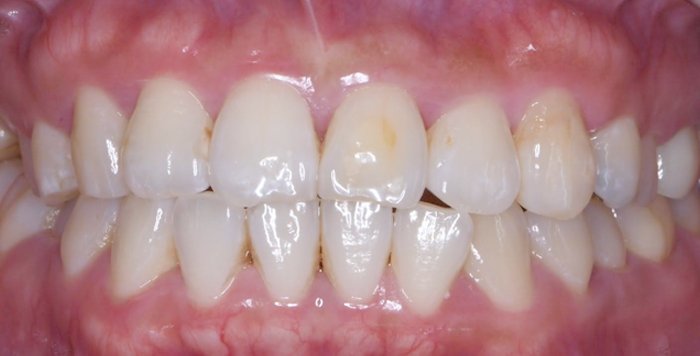

症例3:虫歯を治したい

治療前

治療後

治療中の様子

修復した最後に、酸素で阻害された表面(Oxygen Inhibitation Layer)を最終重合しています。

| 主訴 | 虫歯を治したい |

|---|---|

| 治療期間 | 1日 |

| 治療費 | ¥44,000×2歯(¥88,000) |

| 治療内容 | 象牙質まで達する隣接面の虫歯をラバーダム防湿下にて、コンポジットレジン修復を行いました。歯と歯が適切に接触するよう丁寧に処置を進めました。治療後の見分けがつかないくらい、綺麗に修復できました。 |

| 治療のリスク | 欠けたり、経年的な変色の可能性があります。 |